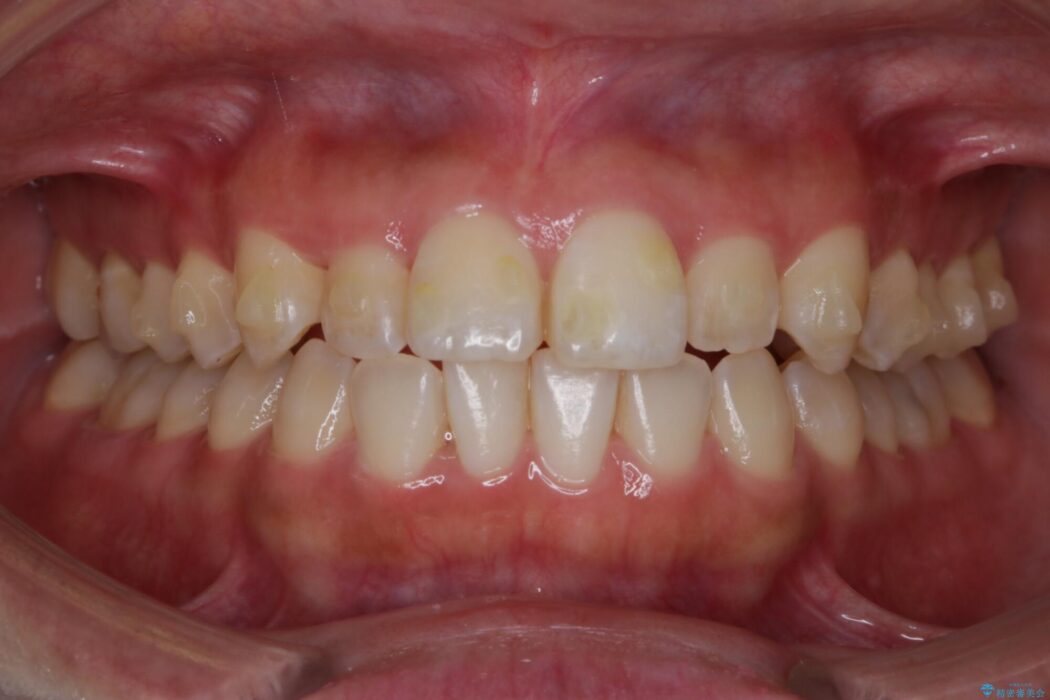

前歯の一部に反対咬合が見られ歯列がガタガタしていたためインビザラインでの矯正治療をご提案しました。

反対咬合の歯も整ったアーチに収まり、きれいに仕上がりました。